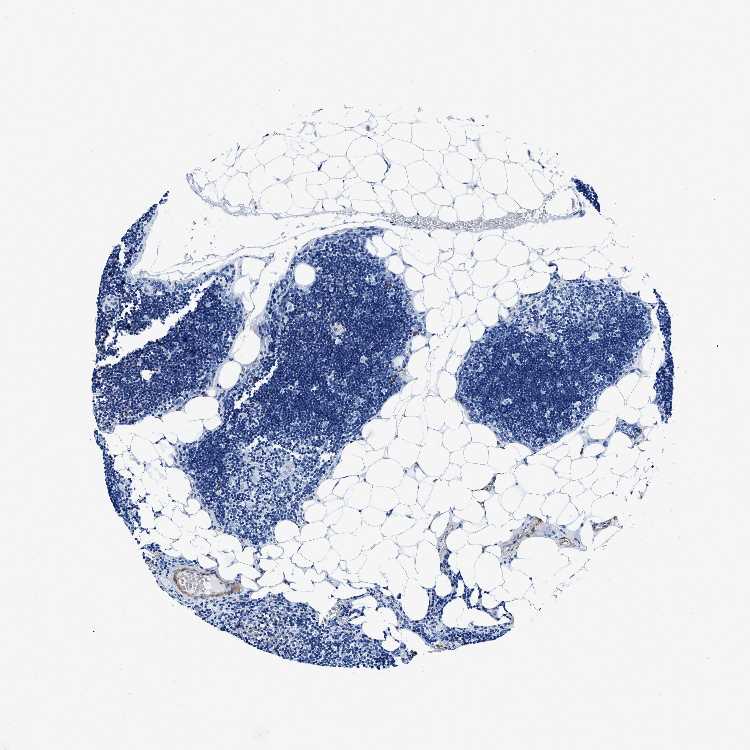

TISSUE PRIMARY DATA LYMPH NODE Show tissue menu

Lymph node

LYMPH NODE - Antibody stainingi

Antibody staining in the annotated cell types in the current human tissue is reported as not detected, low, medium, or high, based on conventional immunohistochemistry profiling in selected tissues. This score is based on the combination of the staining intensity and fraction of stained cells.

Each image is clickable and will lead to virtual microscopy that enables deeper exploration of all samples and also displays staining intensity scores, fraction scores and subcellular localization as well as patient and tissue information for each sample.

Antibody HPA016631

Germinal center cells Not detected

Non-germinal center cells Not detected